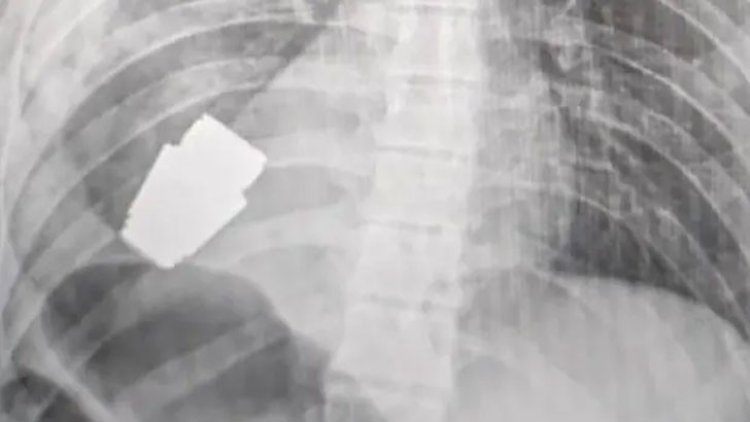

প্রথম নিউজ, অনলাইন ডেস্ক : এক ইউক্রেনীয় সেনার বুক থেকে সার্জারির মাধ্যমে অবিস্ফোরিত একটি গ্রেনেড সফলভাবে অপসারণ করা হয়েছে। কিয়েভের এক জ্যেষ্ঠ কর্মকর্তার বরাতে ব্রিটিশ গণমাধ্যম দ্য গার্ডিয়ান এ খবর জানিয়েছে। ইউক্রেনের উপমন্ত্রী হান্নান মালিয়ার বলেন, আহত ইউক্রেনীয় সেনারা বুক থেকে বিস্ফোরক দ্রব্যটি সরিয়ে ফেলতে সক্ষম হন সার্জনরা। ওই গ্রেনেডের ছবিও প্রকাশ করেছেন চিকিৎসক। যেটিতে স্পষ্ট গ্রেনেডটি দেখা যাচ্ছে। ফেসবুকে দেওয়া এক পোস্টে তিনি জানান, সামরিক চিকিৎসকরা ওই সেনারা শরীর থেকে (VOG) গ্রেনেড অপসারণের একটি গুরুত্বপূর্ণ অপারেশন করেছেন।

ইউক্রেনের অভ্যন্তরীণ বিষয়ক মন্ত্রীর উপদেষ্টা আন্তন গেরাশচেঙ্কো বলেন, অস্ত্রোপচারের সময় ইলেক্ট্রোকোগুলেশন ব্যবহার না করেই অপারেশন করা হয়েছিল। কারণ গ্রেনেডটি যেকোনো মুহূর্ত বিস্ফোরিত হওয়ার আশঙ্কা ছিল। তিনি বলেন, অস্ত্রোপচারের সময় বোমা ডিসপোজাল স্কোয়াডের দুই সদস্য উপস্থিত ছিলেন। যদিও আর বিস্ফোরণ হয়নি। এখন ওই সেনাকে নিবিড় পর্যবেক্ষণে রাখা হয়েছে। একটি ছবিতে দেখা গেছে অস্ত্রোপচারের পর সার্জন বিস্ফোরকটি হাতে ধরে রেখেছেন।

বৃহস্পতিবার ভোরে এক টেলিগ্রাম পোস্টে গেরাশচেঙ্কো লিখেছেন, গ্রেনেডের অবিস্ফোরিত অংশটি হৃদপিন্ডের নিচ থেকে নেওয়া হয়েছিল। গ্রেনেডটি বিস্ফোরিত হয়নি, তবে এটি বিস্ফোরক ছিল।